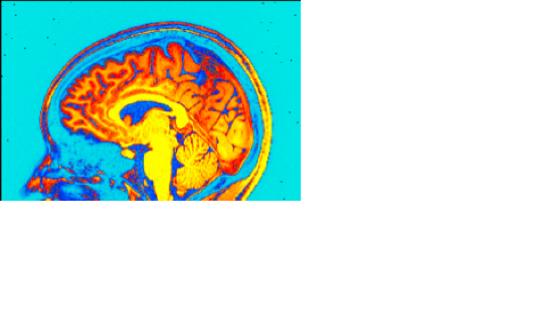

And now tweak the top of the range until it looks cool. Obviously, this is a pretty subjective point, but I try to make the brain all one color and the not-brain next to it a different color.

Navigate to a slice in each view that is pretty. Again, pretty subjective, but it should look like a brain, be as symmetric-looking as possible, and not appear to have a chunk missing. Try your best not to make it look like there's something deathly wrong with their brain. I find that a point in the thalamus a few slices away from the midline tends to make a nice brain picture in all three views. Now, save the images. You can choose the format by right-clicking on the "Sav1.<ext>" button at the bottom of each of the display windows. The default on the version I have installed is .jpg, and that's what I like to use. Left-click this button, and a new window will appear where you can choose the name of the image you want to save. Do this for all three views.